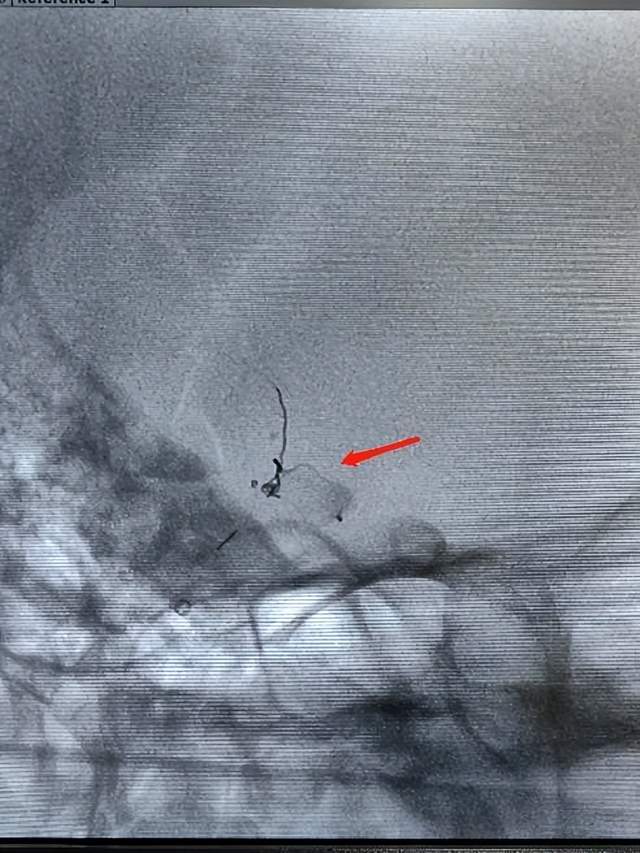

术前图片

全脑血管造影检查显示,此患者的动脉瘤位于前交通动脉,瘤体大小约5.58*5.57*7.74(mm),瘤颈口宽约4.82mm,瘤颈部见一突起小子囊。如行常规的动脉瘤栓塞手术,需行颅内支架辅助栓塞,术后长期双抗的使用引发出血的风险极高。